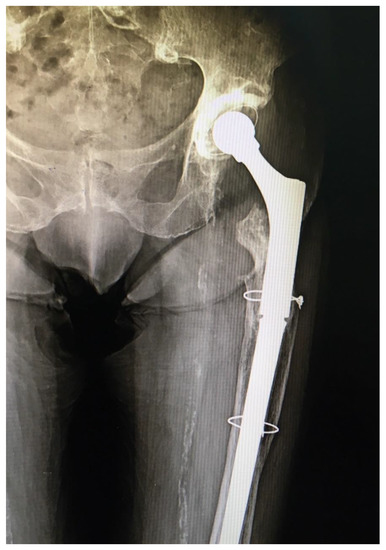

The patient was stable throughout the duration of the surgery, with a total blood loss of 300 mL. On the second postoperative day, the patient started physical therapy, and she was verticalized with the walker. There were no perioperative complications and two and half years after surgery the patient is feeling well, has no pain in the operated hip, and walks with a walker because of her poor general condition. She has had no hip dislocations since this last operation. Postoperative follow-up X-rays show a stable hip endoprosthesis (Figure 2).

Figure 2. X-ray of the operated hip ten months after the surgery, showing a good position of the revision total hip endoprosthesis and no signs of instability.